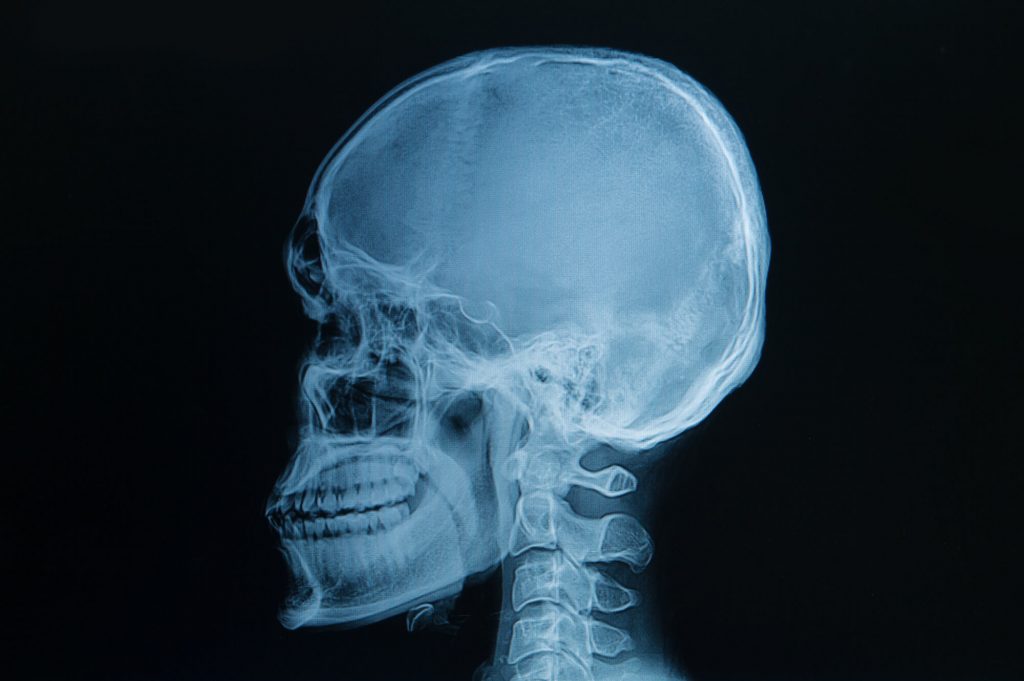

Cephalometric ("ceph") x-rays produce a profile view of the complete head. Orthodontists frequently use these to diagnose bite abnormalities and jaw misalignment.